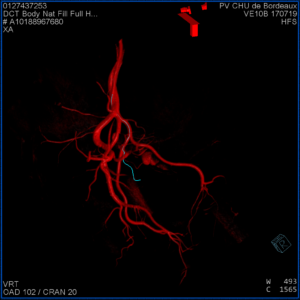

Les artères prostatiques connaissent de nombreuses variantes d'où la difficulté potentielle du geste. Il peut exister une à deux artères par côté (1,4 en moyenne). Le diamètre des artères prostatiques est d'environ 1 mm. L'origine de ces artères est très variable en fonction des patients ce qui rend ce geste difficile. Une acquisition 3D permet de repérer la ou les artères prostatiques et de les cathétériser à l'aide d'une superposition entre l'image 3D et l'image radiographique.

Une fois placé dans l'artère prostatique, on s'assure par des acquisitions 3D de l'absence d'anastomose et donc l'absence de risque d'embolisation hors cible. Puis, on injecte des microparticules (diamètre moyen de 300 à 500 microns) jusqu'à arrêt complet du flux. Ces microparticules peuvent être remplacées ou complétées par l'injection d'un agent liquide (Onyx® ou Glubran®) en fonction de la configuration vasculaire qui ont l'avantage de réaliser une occlusion complète et définitive du vaisseau cible avec une meilleure visualisation à l'injection.